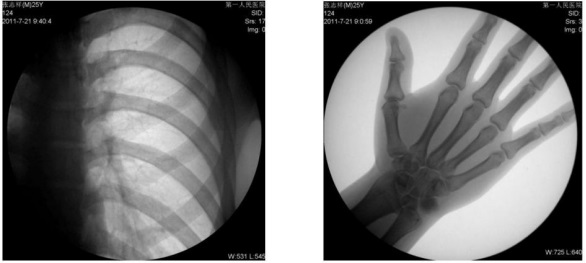

1、數字化透視:適用于全身各部位透視(如胸透、腹透等)。

動態采集速度≥25 幀/秒,主要應用于臨床各科室,尤其是體檢科、內科、外科、骨科、創傷科、急診科等。

1) 胸部檢查:能實現全胸透視動態觀察,對于需要在透視下動態觀察的病變,如肺部腫瘤、氣管異物等可進行實時點片。胸部透視是體檢中的常規檢查項目,臨床意義在于檢查有無肺癌, 特別是早期肺癌。使用胃腸機可通過胸部透視雙肺,縱膈有無病變,以確定病變部位的部位、大小、密度,與周邊組織關系,常見的疾病,如肺炎、肺結核等。胃腸機可以從各種角度動態詳細觀察肺、心臟或其他胸部的病變,對病變的情況可以有個比較全面地了解。